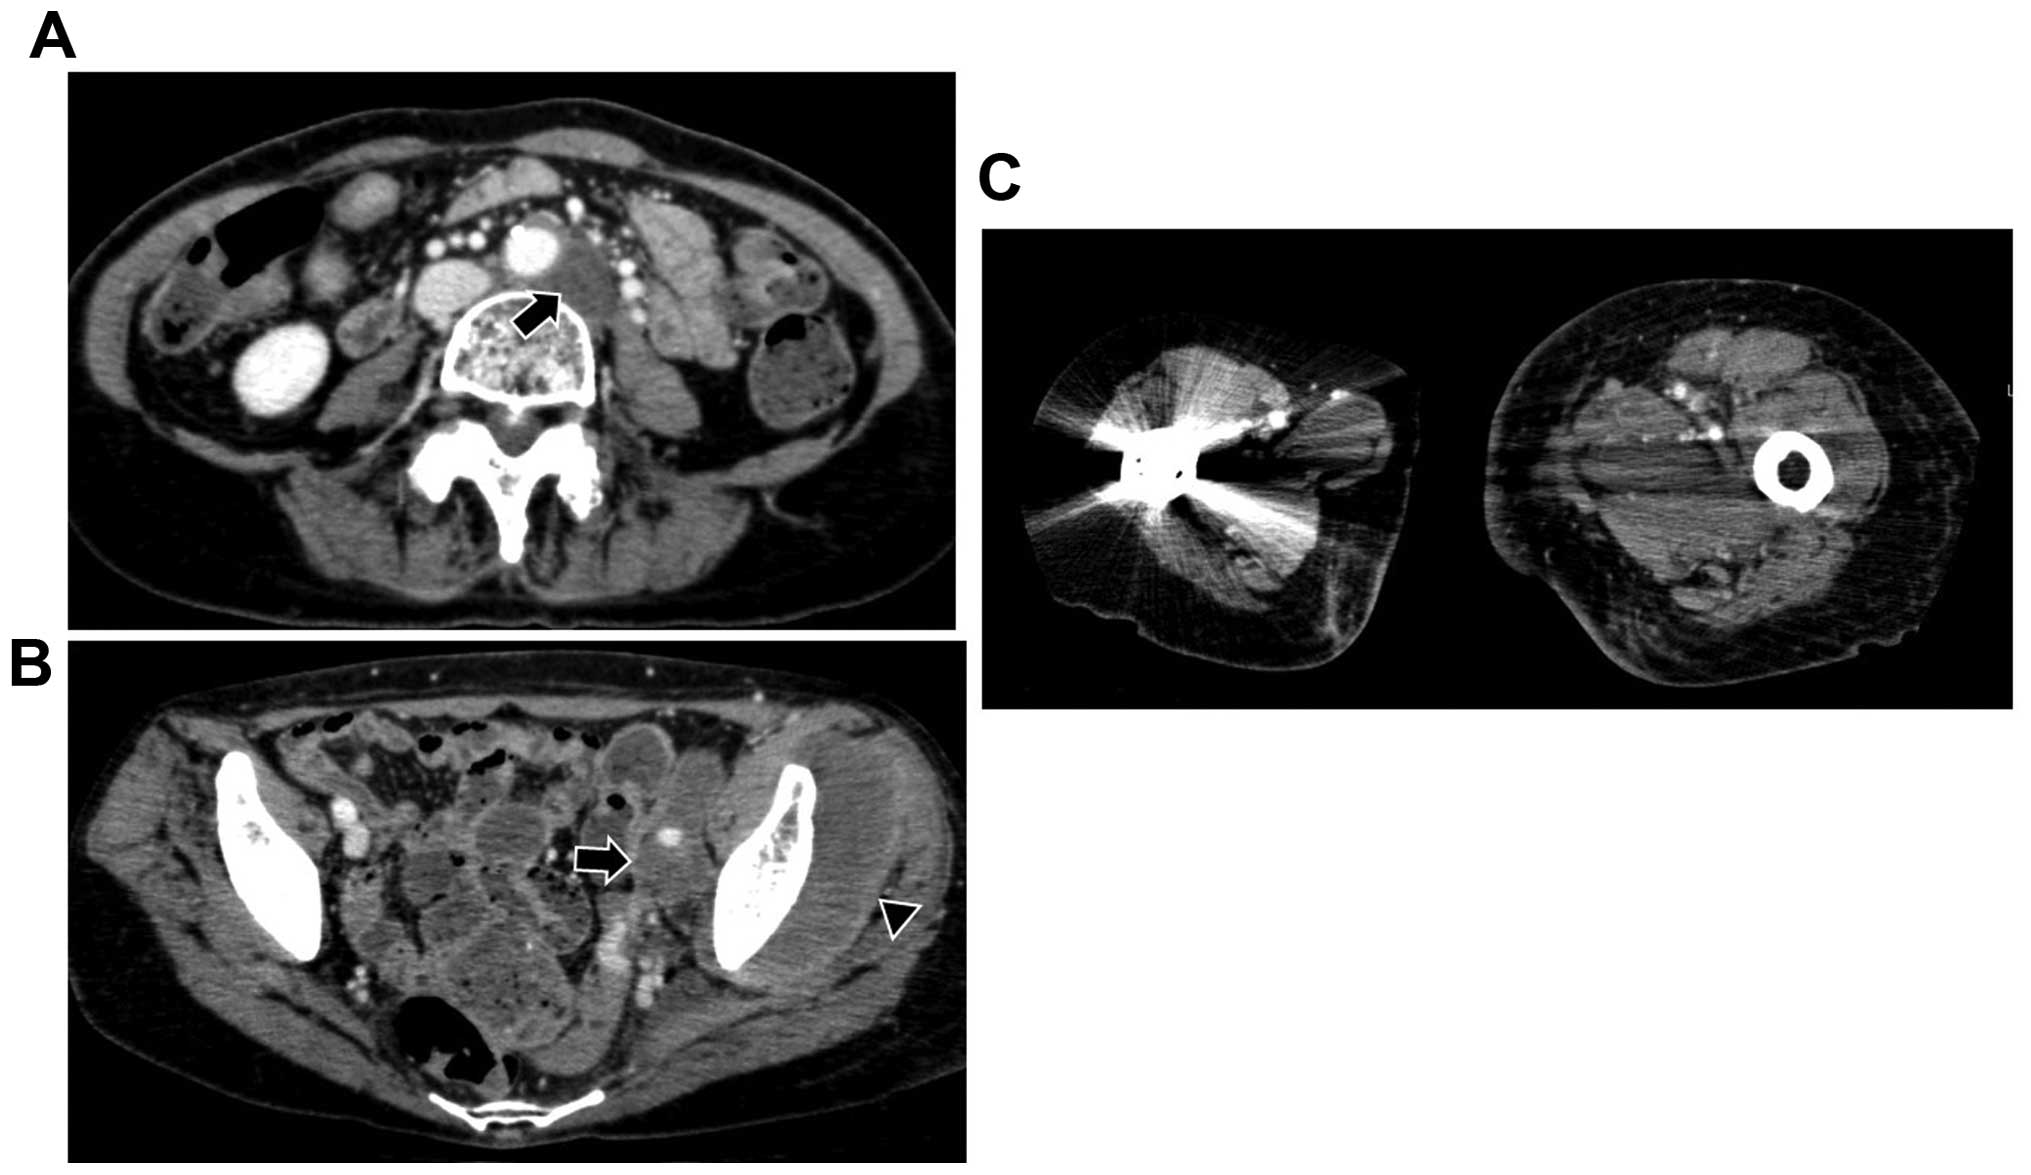

Floating Fetus A Rare Complication Of Balloon Tamponade Treatment

Floating Fetus A Rare Complication Of Balloon Tamponade Treatment

Floating Fetus A Rare Complication Of Balloon Tamponade Treatment

Lower Limb Lymphedema In Lung Adenocarcinoma Two Case Reports